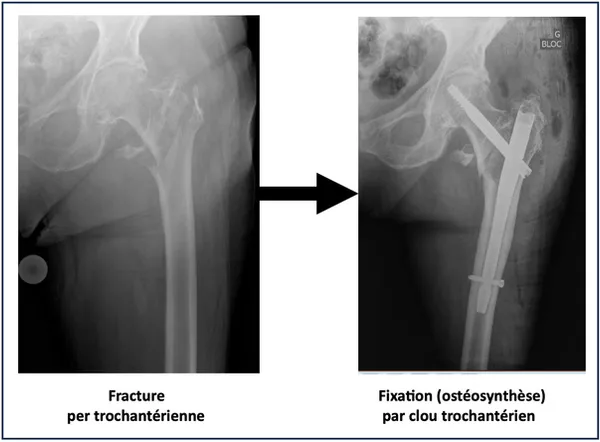

Une radiographie du bassin confirme la fracture. On observe une perte de continuité du massif trochantérien souvent associée à un déplacement du trochanter et du col du fémur. Il n’est en règle générale pas nécessaire de réaliser d’autres examens.

Le traitement de référence est l’ostéosynthèse : les fragments osseux sont remis en bonne position et fixés avec un clou trochantérien ou une vis-plaque, qui permet une reprise rapide de la marche et une disparition des douleurs. Le choix entre ces deux options dépend du type de fracture et sera à discuter avec votre chirurgien.